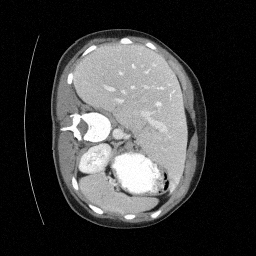

Training an NCSN on Abdomen CT - I

Figure 2: Some example images from the validation split.